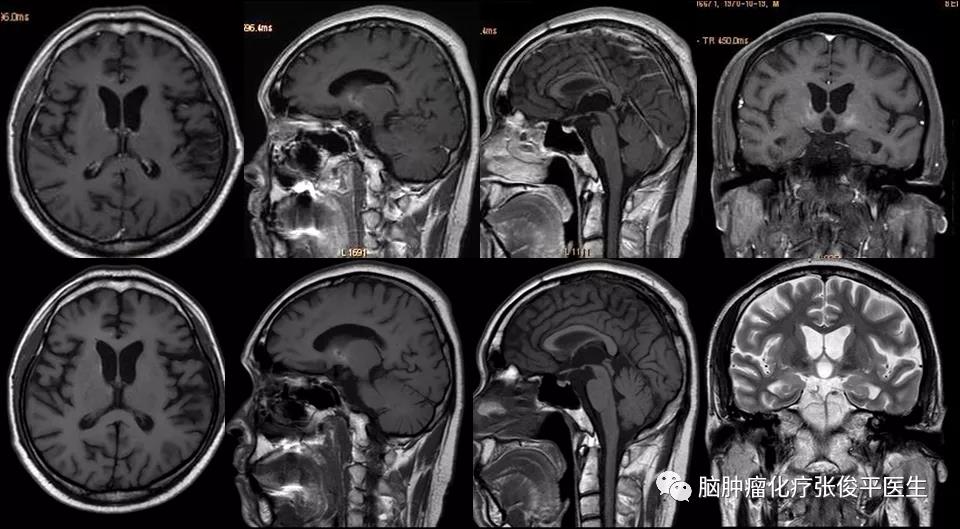

化疗2周期后复查头颅核磁(如图2)显示颅内肿瘤消失,未见异常强化,患者症状明显改善,疗效评价CR(完全缓解)。

图2. 2010-8-30核磁(上行为增强相,下行为平扫相),化疗2周期后,颅内未见明显强化,疗效评价CR。